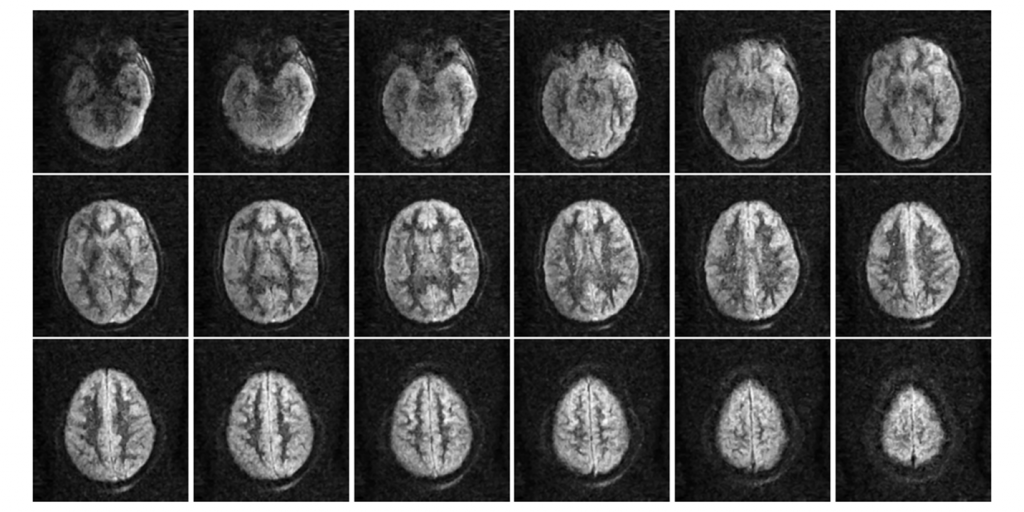

Full Body Insight is an emerging company (spin-off) of the Universitat Politècnica de València (UPV) dedicated to the creation of different medical imaging devices, such as PET or MRI, which make use of a disruptive technology, in order to improve the quality of life of patients.